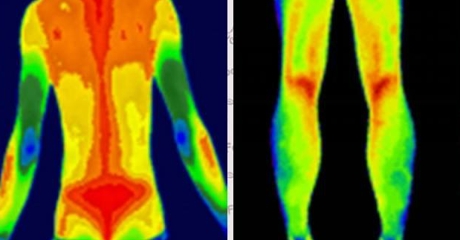

(插入示意圖:脊柱炎癥熱圖 – 紅色熱區(qū)與MRI病灶位置完全吻合)

乳腺癌:患側(cè)乳頭溫度升高0.5-2℃

甲狀腺癌:腫瘤區(qū)域呈現(xiàn)“熱島效應(yīng)”